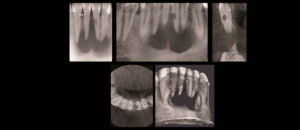

192 – Clasificación propuesta para los contactos interproximales de los molares primarios utilizando CBCT: Un estudio piloto

El «Área de contacto» es un término que se usa para denotar las alturas proximales del contorno de las superficies mesial y distal del diente.